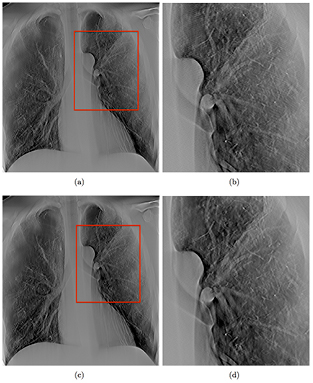

Standard image High-resolution imageTwo sets of tomosynthesis images, both covering the same 34° angular span and acquired with same total mAs, but with different numbers of projection images, were compared. Figure 13(a) shows a slice reconstructed with 32 projections covering 34°, acquired at 80 kVp and 0.6 mAs, while figure 13(c) shows the same slice reconstructed with 85 projections over the same angular span. Increasing the number of projections results in reduced ripple artifacts as shown magnified in figures 13(b) and (d), corresponding to the region boxed in red in figures 13(a) and (c), respectively. At the same angular coverage, more projection views decreases the angular step between projection views and reduces the under sampling of the sharp edges.

Figure 13. (a) shows a slice reconstructed with 29 projections over 34° angular span, while (c) shows the same slice reconstructed with 85 projections over the same angular span. As shown in the zoomed in region, outlined with a red box in (b) and (d), it can be seen that the ripple artifacts decreased when the number of projection images is increased. The two sets of images were acquired at the same total dose.